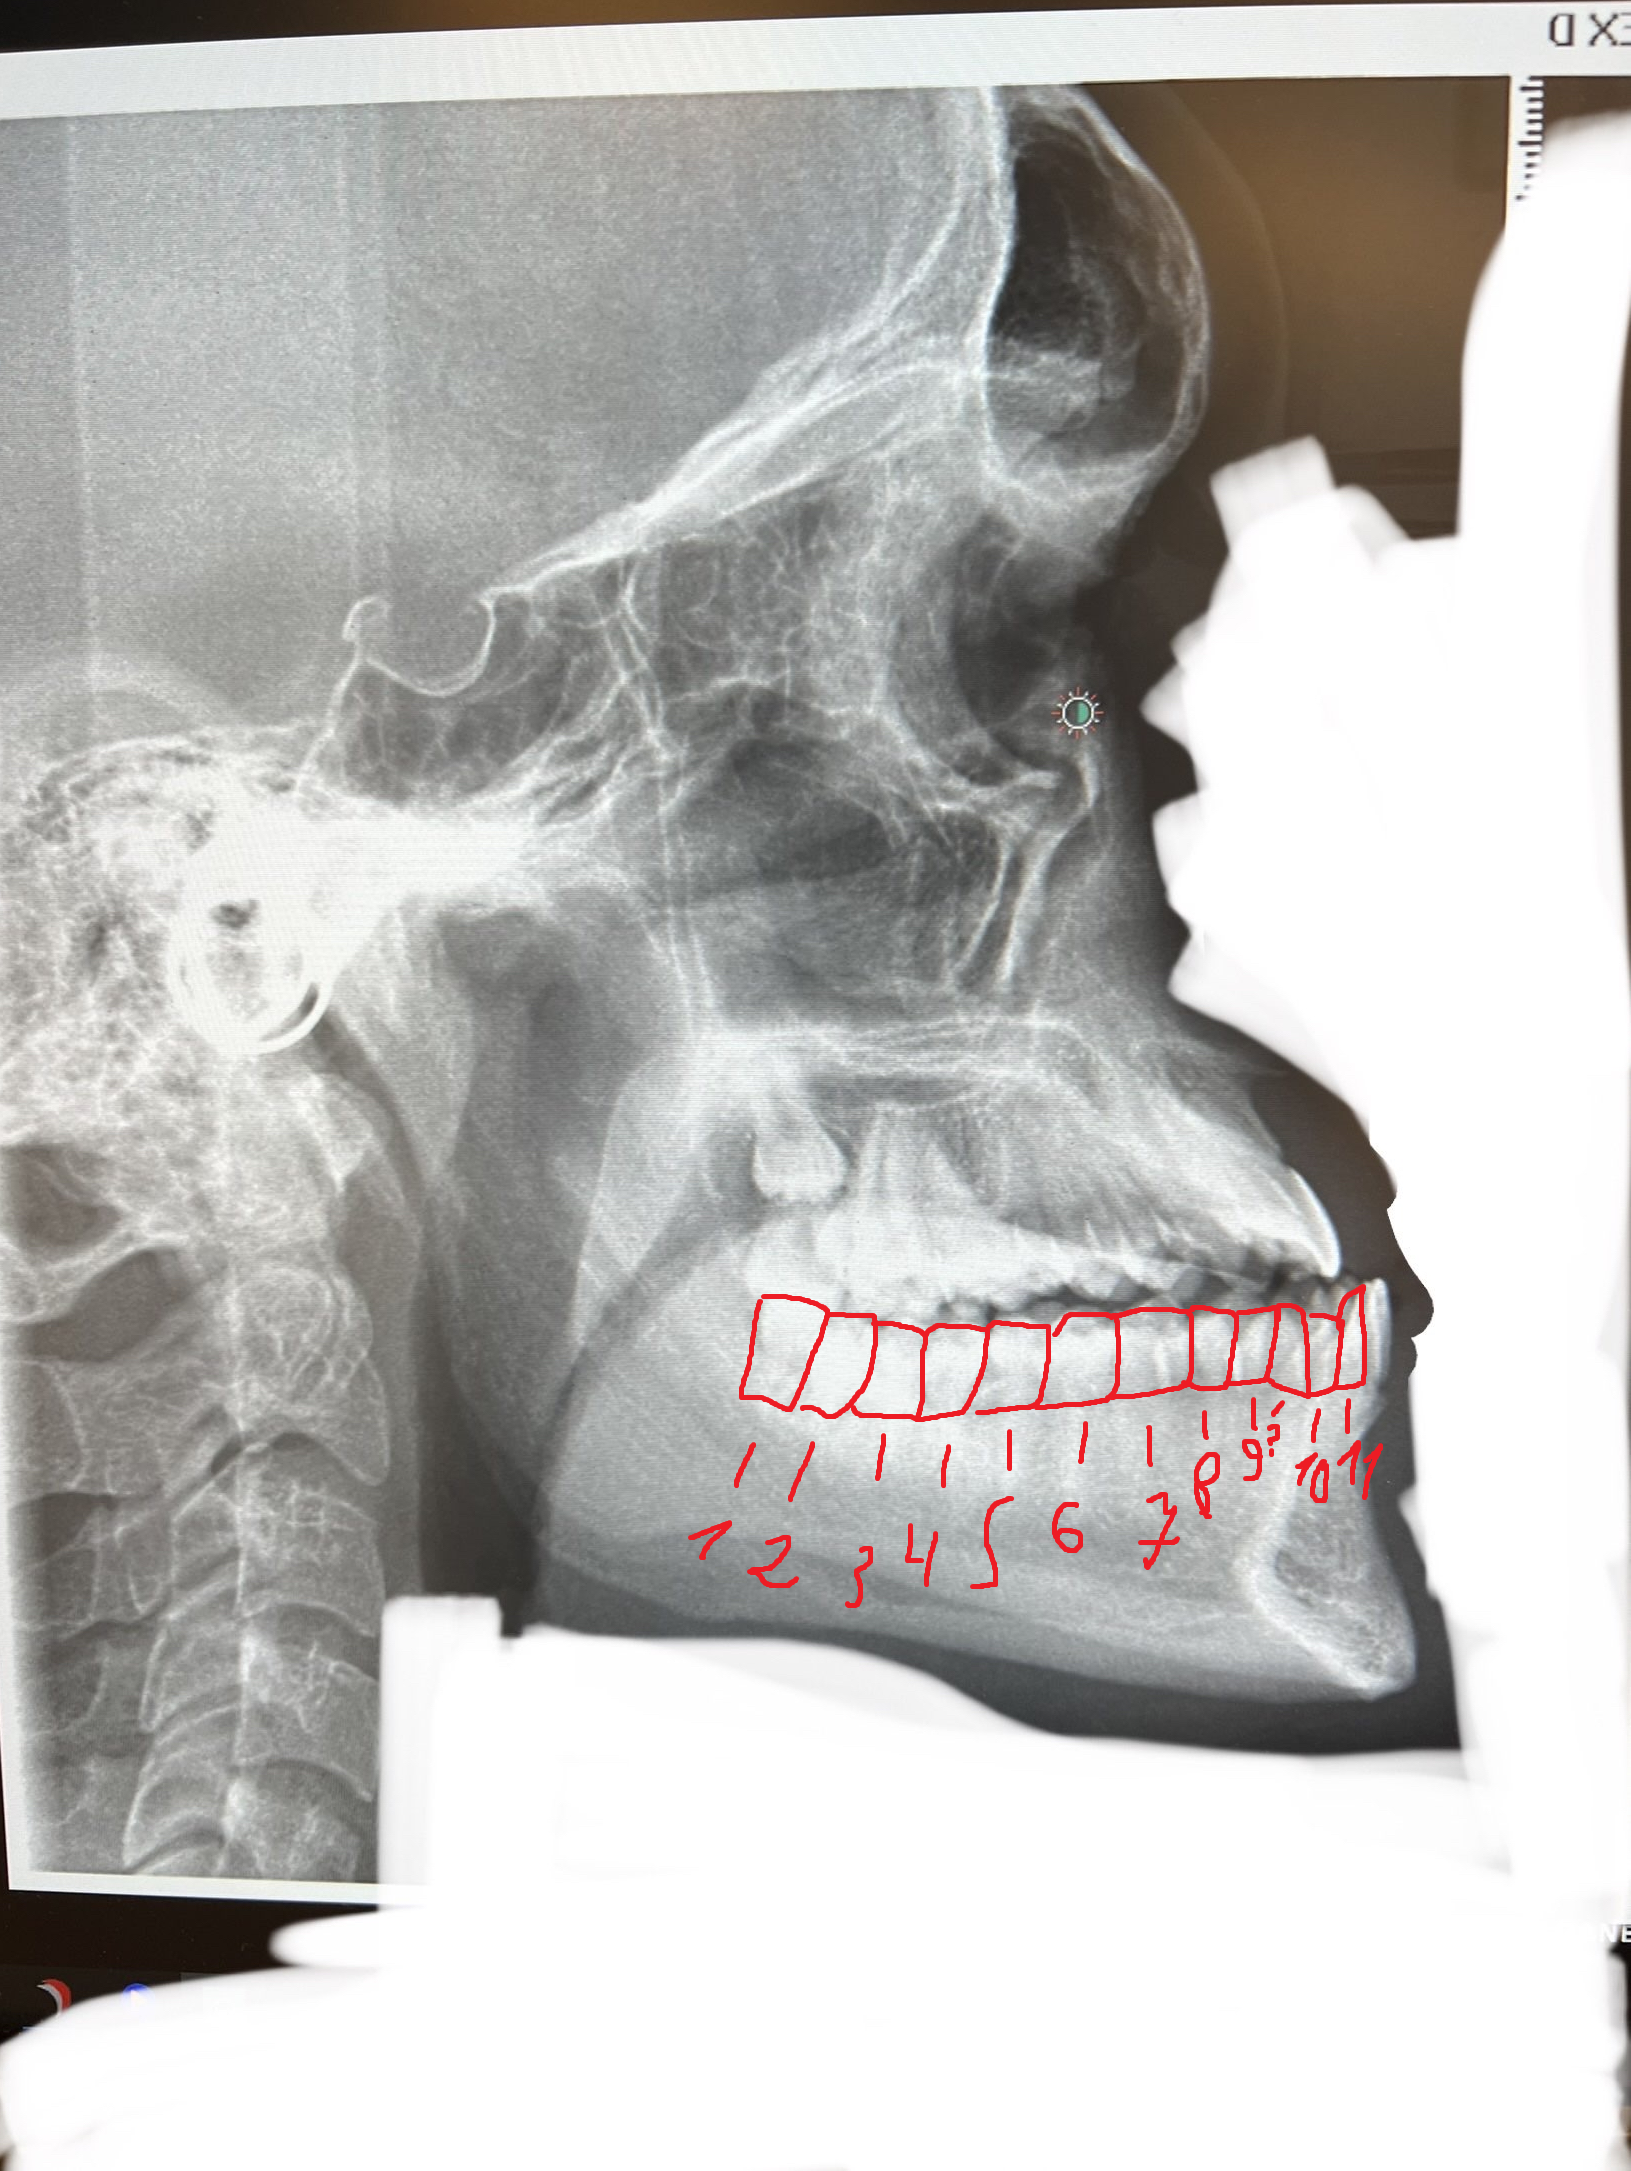

This person with a textbook class 3 and an exceptionally wide airway (probably around 3 times larger than average), could undergo DJS with significant maxillary movement and end up mogging while still preserving their airway size.

For example:

wth are ts photo, 11 teeth on the bottom side :forcedsmile::forcedsmile::forcedsmile: